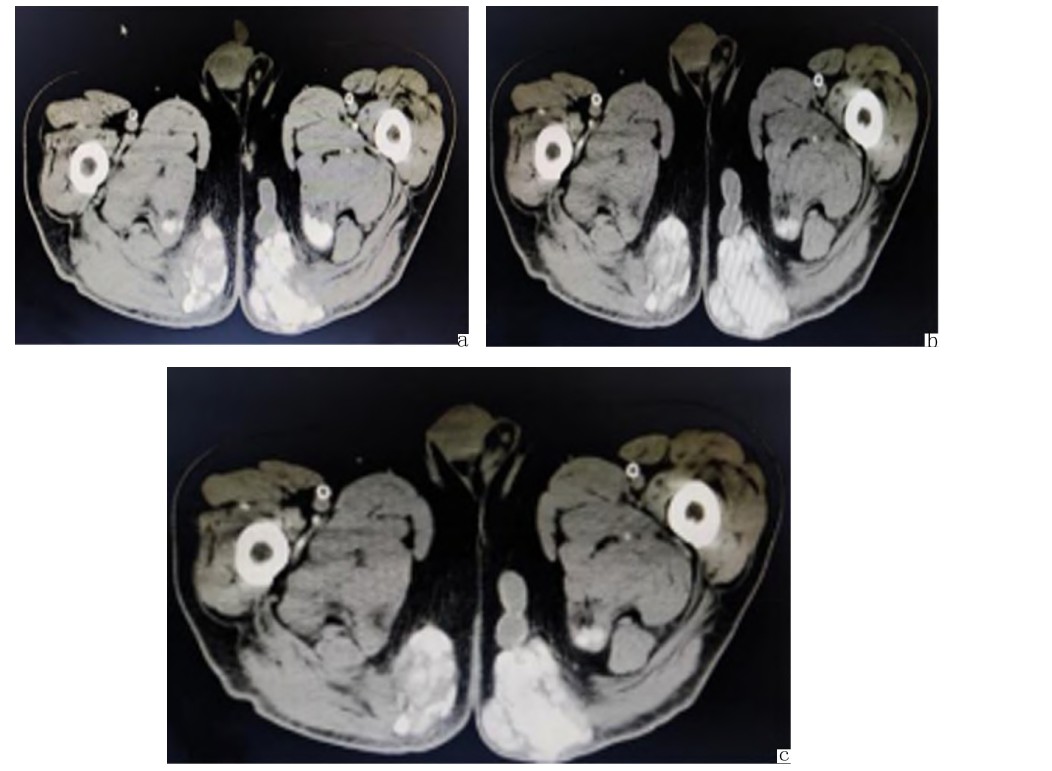

辅助检查:实验室检查:中性粒细胞百分比79.30%,淋巴细胞百分比12.90%。尿素 17.39mmol/L,肌酐130.0μmol/L,尿酸 602μmol/L,估算肾小球滤过率51mL/(min·1.73m2)。血沉、CRP、肝功能未见明显异常。尿常规pH值5.00。盆腔螺旋CT回示(见图1):右肾小结石;多发关节周围、臀部软组织高密度影及骨质改变。左侧浅表包块彩超回示(见图2):左侧臀部皮下组织混合回声团,请结合临床。诊断:(1)皮下组织肉芽肿(左侧臀部痛风性肉芽肿),(2)右侧臀部肿物,(3)全身多发痛风石形成,(4)原发性高血压3级 很高危组并心脏损害,(5)冠状动脉粥样硬化性心脏病,(6)冠状动脉支架植入后状态,(7)2型糖尿病,(8)慢性肾衰竭。

盆腔螺旋CT图